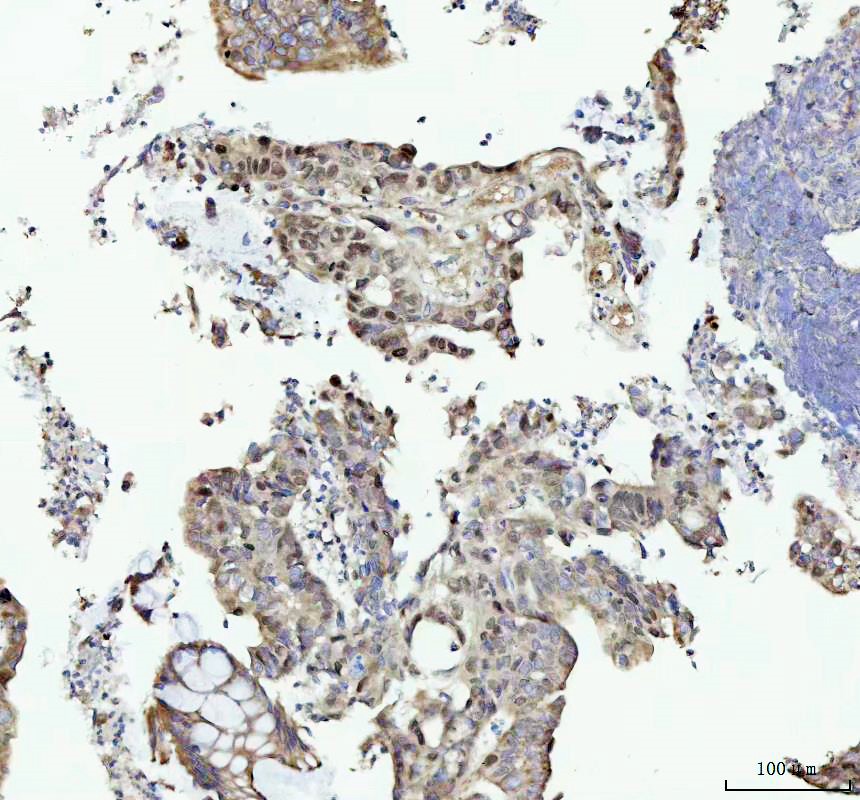

IHC analysis of MCM4 using anti-MCM4 antibody (M02301) .

MCM4 was detected in a paraffin-embedded section of human colorectal adenocarcinoma tissue. The tissue section was incubated with rabbit anti-MCM4 Antibody (M02301) at a dilution of 1:200 and developed using HRP Conjugated Rabbit IgG Super Vision Assay Kit (Catalog # SV0002) with DAB (Catalog # AR1027) as the chromogen.